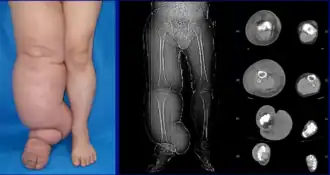

Diagnosis is generally based on signs and symptoms, with testing used to rule out other potential causes.[2] An accurate diagnosis and staging may help with management.[2] A swollen limb can result from different conditions that require different treatments. Diagnosis of lymphedema is currently based on history, physical exam, and limb measurements. Imaging studies such as lymphoscintigraphy and indocyanine green lymphography are only required when surgery is being considered.[2] However, the ideal method of staging to guide treatment is controversial because of several different proposed protocols.[32][33]

Lymphedema can occur in both the upper and lower extremities, and in some cases, the head and neck. Assessment of the extremities first begins with a visual inspection; color, presence of hair, visible veins, size and any sores or ulcerations are noted. Lack of hair may indicate an arterial circulation problem.[34] In cases of swelling, the extremities' circumference is measured over time for reference. In early stages of lymphedema, elevating the limb may reduce or eliminate the swelling. Palpation of the wrist or ankle can determine the degree of swelling; assessment includes a check of the pulses. The axillary or inguinal lymph nodes may be enlarged due to the swelling. Enlargement of the nodes lasting more than three weeks may indicate infection or other illnesses (such as sequela from breast cancer surgery) requiring further medical attention.[34]

As described by the Fifth WHO Expert Committee on Filariasis,[43][44] and endorsed by the American Society of Lymphology,[45] the staging system helps to identify the severity of lymphedema. With the assistance of medical imaging, such as MRI or CT, staging can be established by the physician, and therapeutic or medical interventions may be applied: